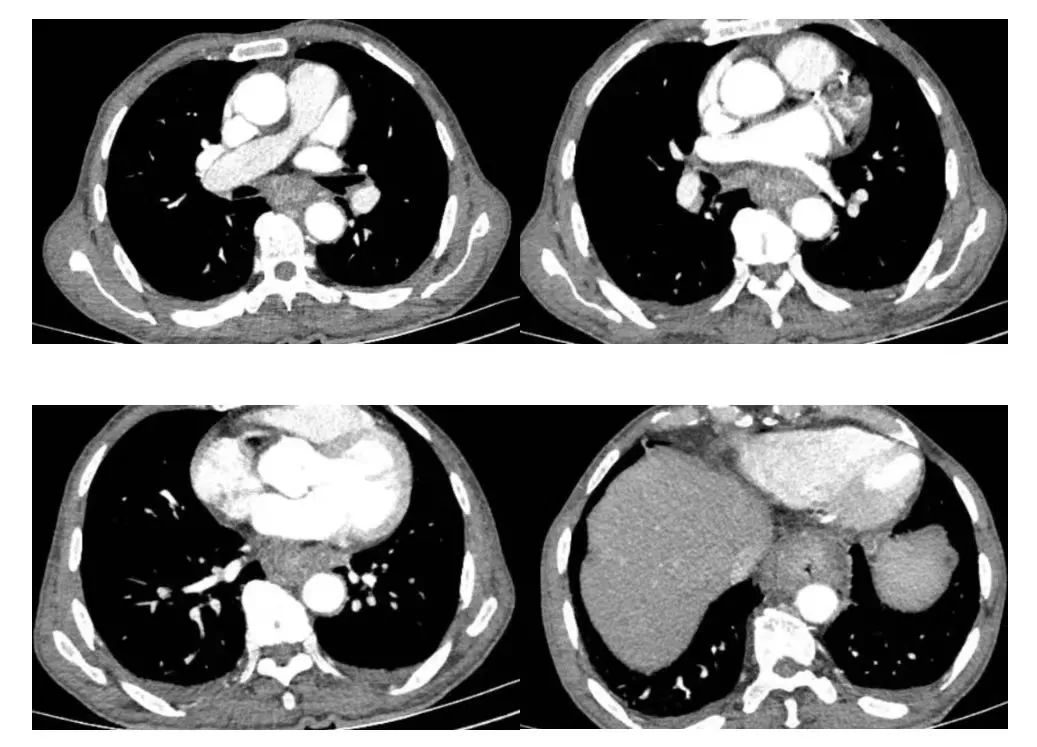

日前,嘉定区中心医院胸外科一位“双肿瘤”患者经历了微创食管癌切除+胃代食管颈部吻合+脾切除手术,顺利出院。

患者刘老伯今年已经76岁高龄,半个月前体检时发现白细胞异常增高,骨髓穿刺确诊慢性粒单核细胞白血病,遂就诊于仁济医院嘉定分院(嘉定区中心医院)血液科,予水化碱化、保肝护胃、止血等对症治疗。

医生进一步询问病史,发现患者有进行性吞咽困难1月余,伴有体重减轻,乏力等症状。胸外科主任李建新在分析病情后考虑食管中下段癌累及贲门胃底可能,患者合并白血病,伴有贫血、血小板减少,营养不良性低蛋白血症,脾功能亢进,有化疗禁忌,若不及时手术干预,情况必然恶化。

面对患者复杂的病情,李建新主持召开多学科联合会诊(MDT)。经与会专家讨论,大家达成共识,认为切除巨脾后有利于经胸腹联合切口显露贲门胃底,解决脾亢所致的血小板减少,于是决定先行手术,解除食管梗阻,术中输注血小板,加强抗感染,积极防治出血,改善情况后,恢复营养摄入,为后续白血病及食管癌的化疗创造条件。

患者刘老伯接受了全麻下食管癌切除+胃代食管颈部吻合+脾切除术。由于整个手术在胸腔镜辅助下进行,切口小、出血少、恢复快,也完全没有传统食管手术的剧烈疼痛不适感,术后不久,刘老伯已经能够正常进食面条、馄饨等半流质食物,目前已顺利出院。下一步,医生将根据患者恢复情况,安排白血病的治疗及食管癌的化疗。